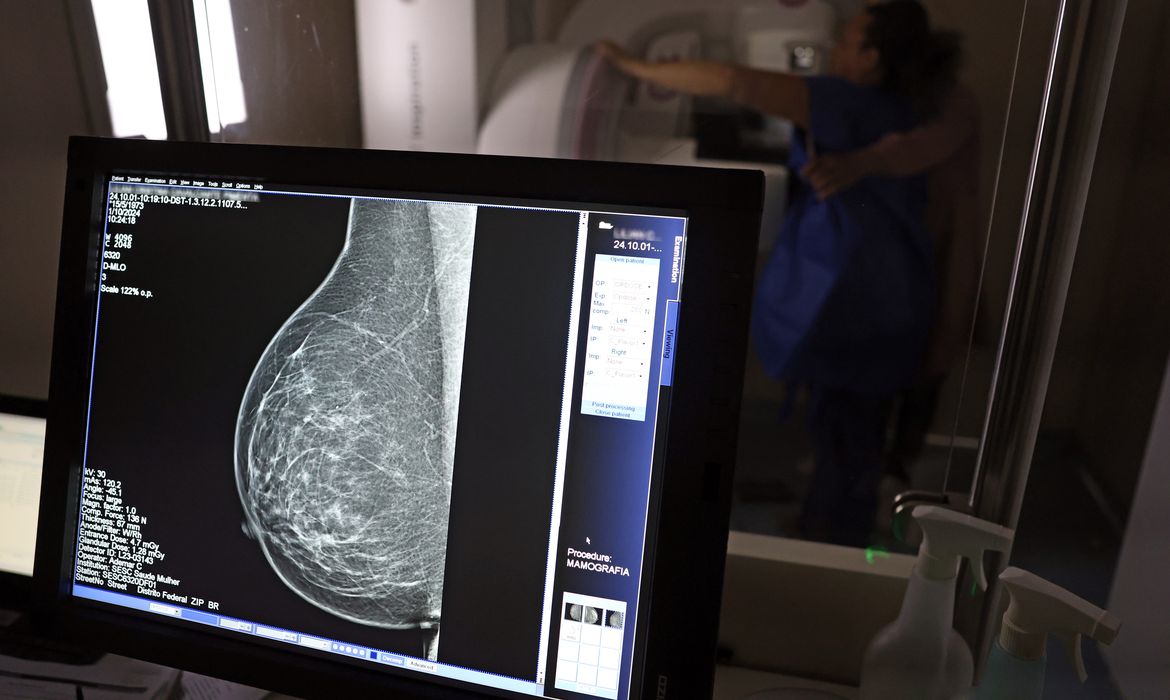

A Advocacia-Geral da União (AGU) informou nesta quinta-feira (20) ter aberto uma ação civil pública contra o médico Lucas Ferreira Mattos, por ele ter dito em postagem nas redes sociais que o exame de mamografia causa câncer de mama

O caso levou os conselhos regionais de medicina de Minas Gerais e São Paulo a abrirem investigações tendo o médico como alvo. O Instituto Nacional do Câncer (Inca) também informou, à época, não haver evidência de que a mamografia possa causar câncer de mama e que, pelo contrário, o exame previne a doença

O órgão anexou ao processo nota técnica do Ministério da Saúde segundo a qual “é recomendado que mulheres de 50 a 69 anos, de risco padrão, façam uma mamografia de rastreamento a cada dois anos. Esse exame pode ajudar a identificar o câncer antes de a pessoa ter sintomas”